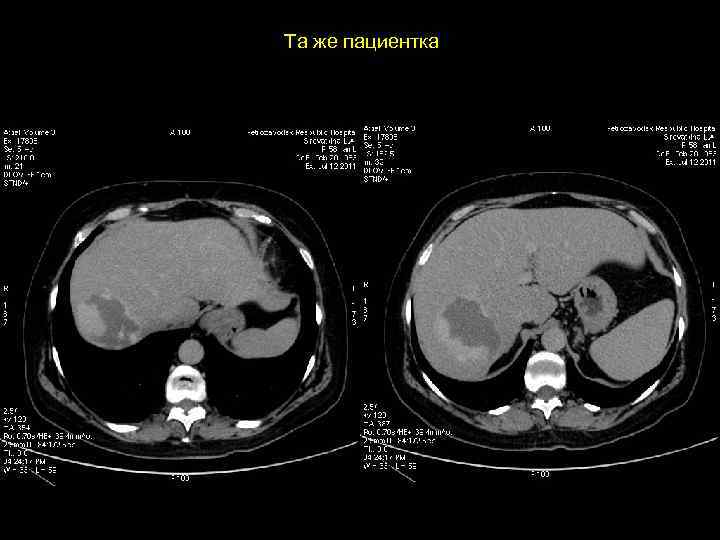

Клиническое наблюдение. Пациентка К, 1966 г. р.

Та же пациентка

АКТУАЛЬНЫЕ ВОПРОСЫ РЕНТГЕНОЛОГИИ ЛУЧЕВАЯ ДИАГНОСТИКА ОЧАГОВЫХ ПОРАЖЕНИЙ ПЕЧЕНИ ФОКУСНАЯ (УЗЛОВАЯ) ГИПЕРПЛАЗИЯ ПЕЧЕНИ Компьютерно-томографическая семиотика: - низкоплотностное образование ( до 30 ед Н ) - без капсулы - при болюсном введении РКВ очень быстро накапливают (в течении 1 -2’) и очень быстро выводят РКВ, вновь становясь низкоплотностными образованиями